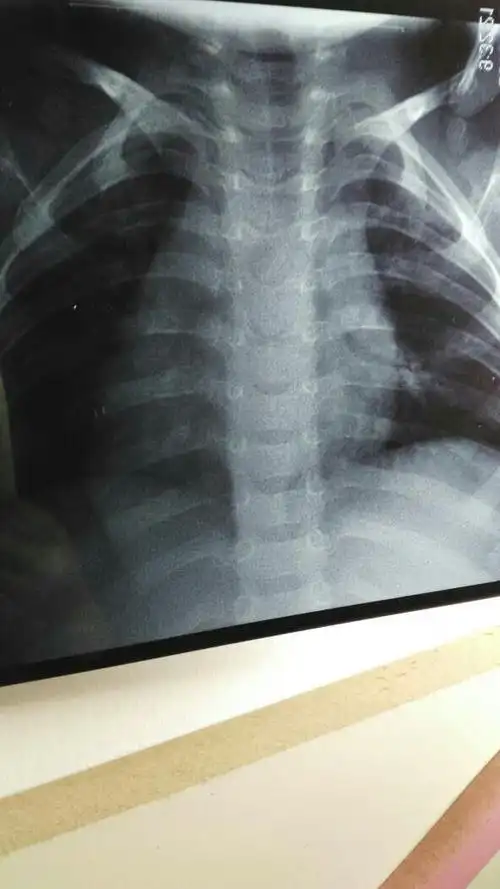

这几组患儿胸片是肺炎还是正常影像规培医师懵了

三个月宝宝肺炎住院三天了,刚开始是咳嗽拍片诊断肺炎的,住院第二天

问题:20天宝宝在医院影像科诊断上写的是 支气管肺炎 该怎么办

小孩两个月了,不发烧,偶尔咳两下,拍片子诊断为支气管肺炎,医请各位